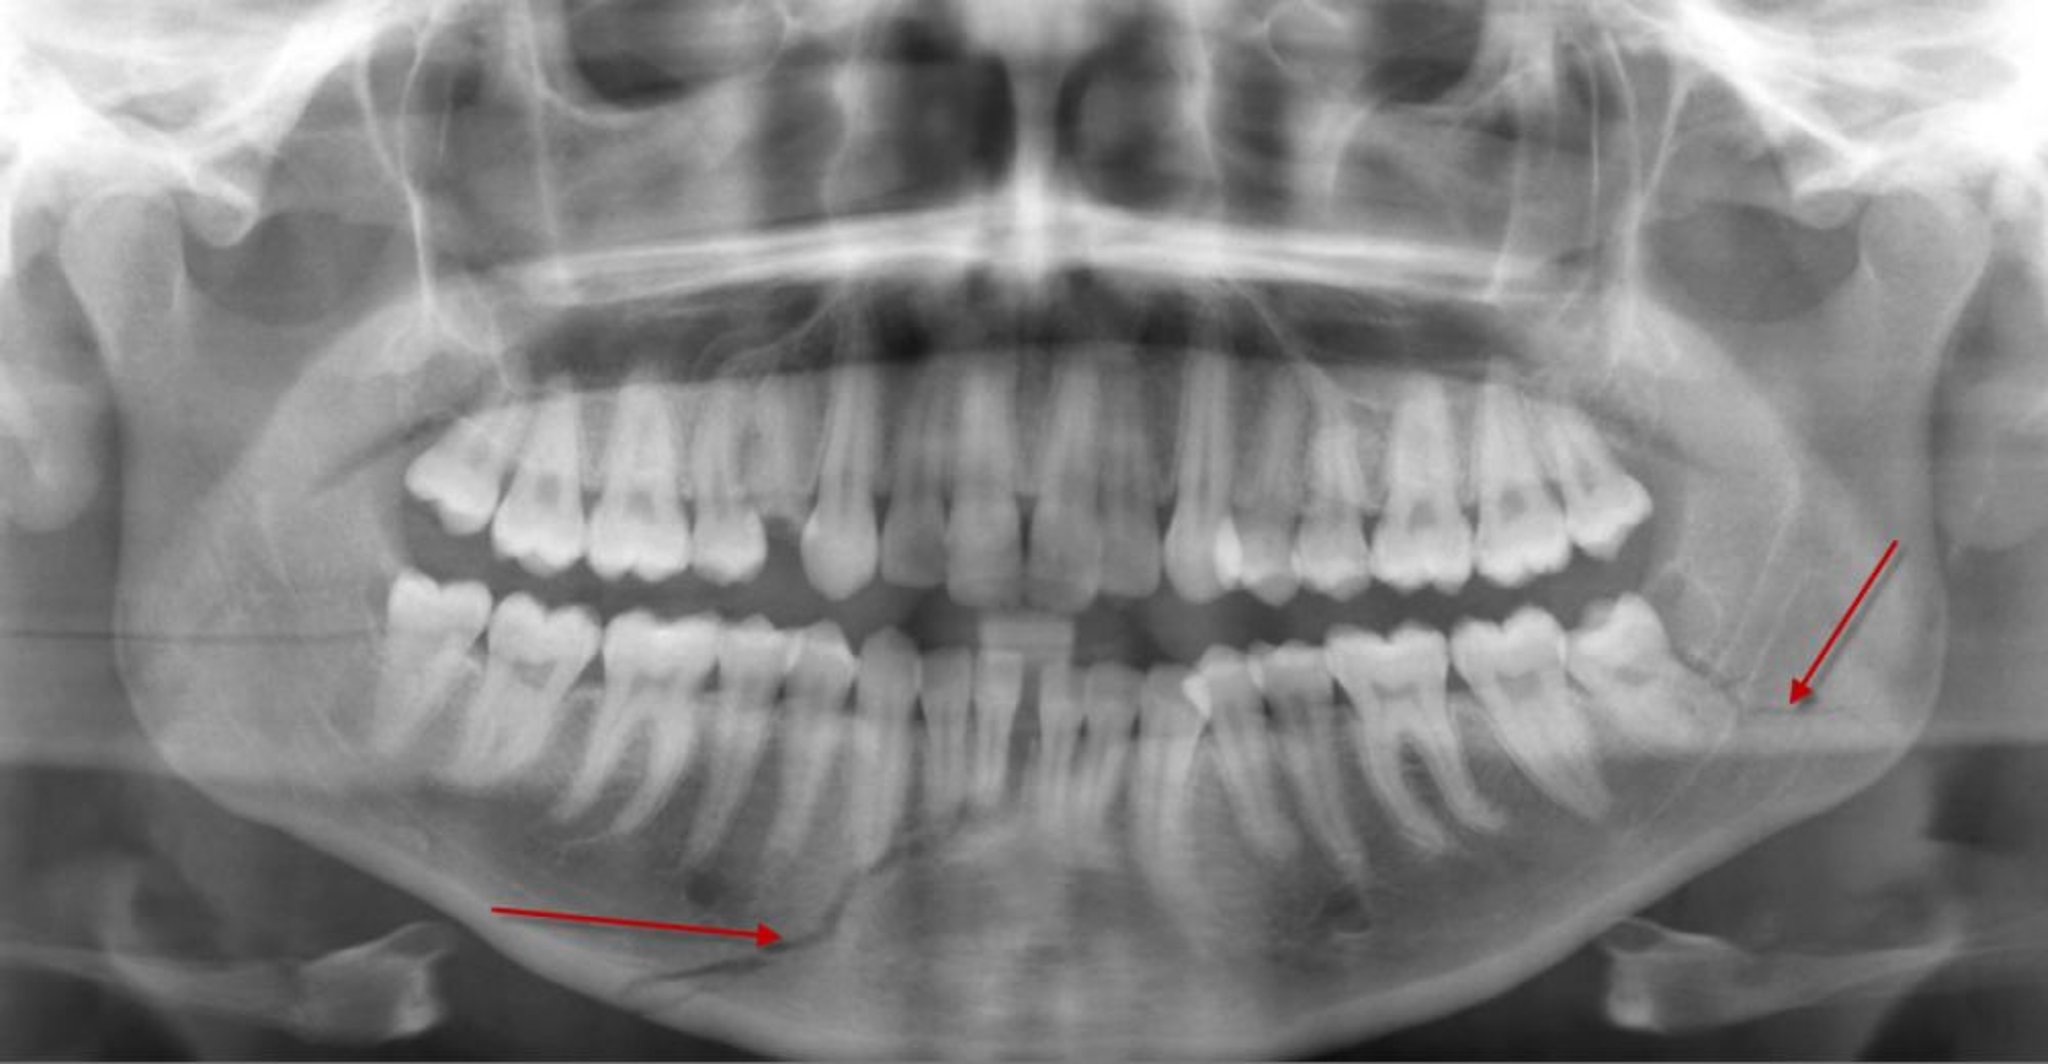

Панорамна рентгенографія зубів є найкращим методом дослідження при ізольованому переломі нижньої щелепи. Для діагностики переломів кісток обличчя проводять комп’ютерну томографію з тонкими зрізами (товщина зрізу 1 мм) в аксіальній і фронтальній площинах.